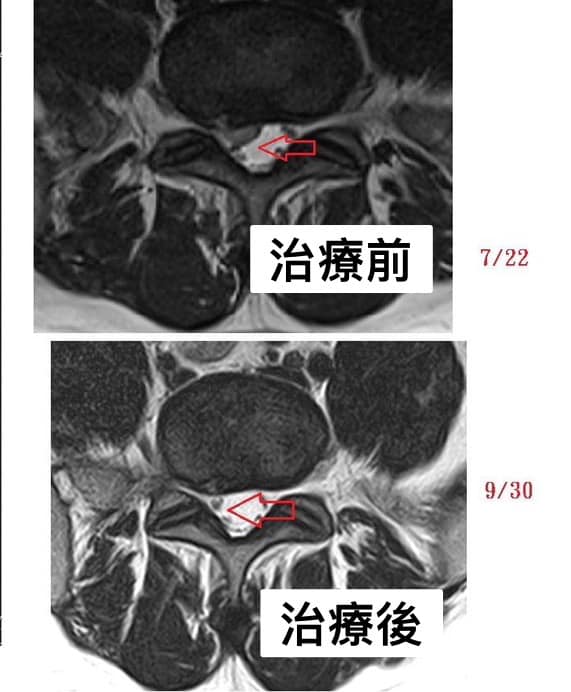

⭕️七週治療椎間盤明顯吸收回去。

感想:每一次看到患者症狀改善很多當然開心,更興奮的是突出的骨刺在術後的核磁共振也發現有吸收的現象!皆大歡喜啊。

⭕️脊椎整合中醫微創療法可在關節面跟惻隱窩減壓,讓椎間盤內的高壓下降,搭配針灸刺激多裂肌與核心肌群的增生,讓脊上韌帶恢復力量,對抗椎間盤突出,自然提供一個很好髓核自行吸收的環境。